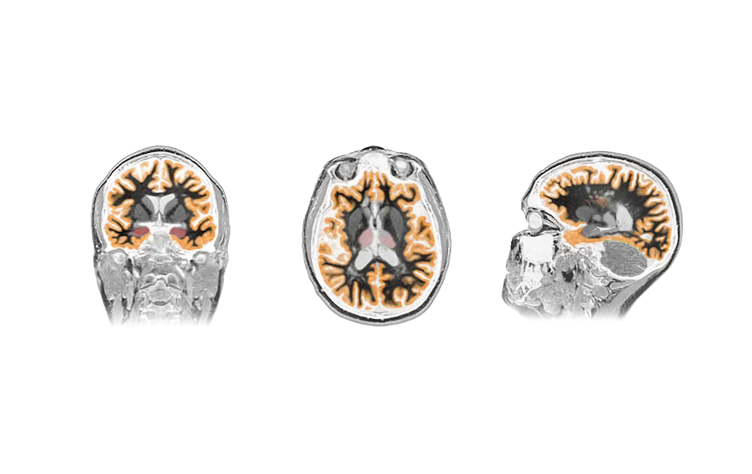

The NeuroQuant® report uses FDA-cleared technology to measure the size of different parts of your brain. It analyzes your MRI scan, calculates volumes of specific structures, and presents the results as both measurements and color-highlighted images. Your values are also compared to people of the same age and sex, helping show whether they fall within the expected range.

Brain structure visualization

Measuring the size of white matter and deep gray matter areas of the brain can help identify patterns that may be associated with certain neurological conditions. When reviewed together with your medical history and other test results, this information may support earlier identification and ongoing monitoring of brain health.